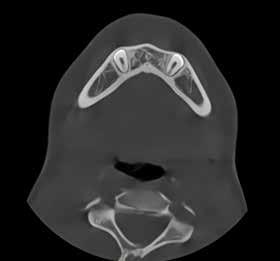

PATIENTTILFÆLDE 1

Patienttilfælde 1 (Fig. 1) er en 37-årig kvinde, henvist efter succesfuld behandling af stadie 3-parodontitis. Der er nu sundt

Før behandling

parodontium, ingen pocher over 4 mm, og både blødnings- og plakindeks er under 10 %. Patienten er motiveret for ortodontisk behandling, da hendes tænder er vandret over tid, delvist som følge af reduceret parodontium.

Der ses anterior trangstilling i begge kæber og overerupterede 1+1 og 2,1-1,2, hvilket resulterer i dybt bid med 2- tæt på ganepåbidning. Der er normale sidetandsrelationer, men der ses 5 mm horisontalt overbid (HOB) og 7 mm vertikalt

overbid (VOB). Papillen mellem 1+1 er betydeligt reduceret pga. fæstetab, og de mesialt kippede 1+1 har resulteret i en ”dark triangle”. Den facioorale funktion er for nuværende i.a. Panoramarøntgen (Fig. 1, I) viser marginalt knogletab i begge kæber og fravær af 8,7+7,8 og 8,7-8.